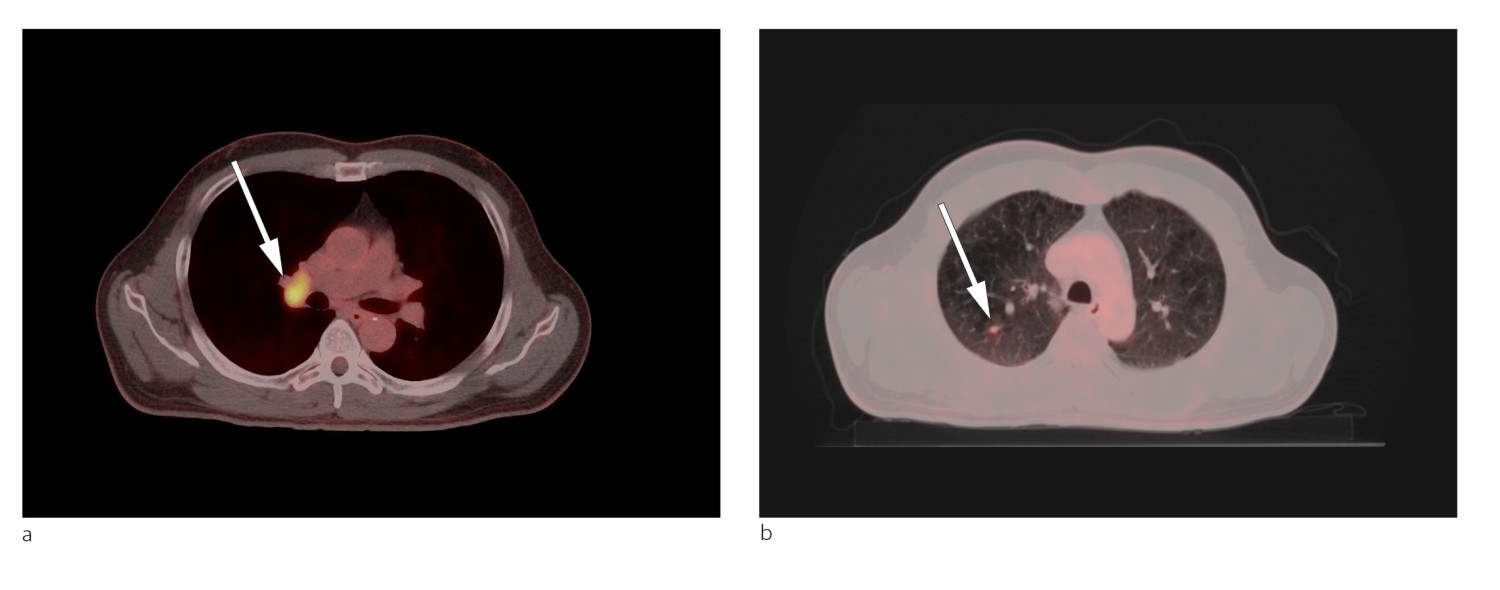

Lungekreft ble ikke påvist på CT thorax, men PET/CT helkropp viste malignitetssuspekte forandringer i høyre lungelapp og høyre hilus (fig 1). Cytologiske funn og biopsifunn fra lymfeknute i mediastinum bekreftet mistanken om småcellet lungekreft. Pasientens tilstand var forenlig med Lambert-Eatons myastenisk syndrom forårsaket av småcellet lungekreft ledsaget av cerebellær degenerasjon.